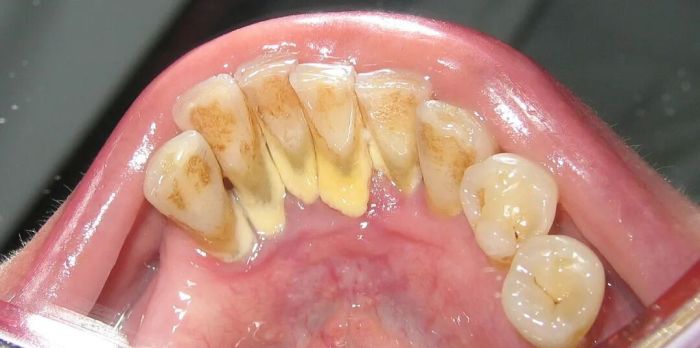

牙齿上的牙结石(牙根处黄色部分)

这也解释了为什么牙结石最容易出现在下门牙内侧、上后牙的外侧,这些位置都是唾液腺开口处,矿物质源源不断供应,堪称牙结石的“高产区”。